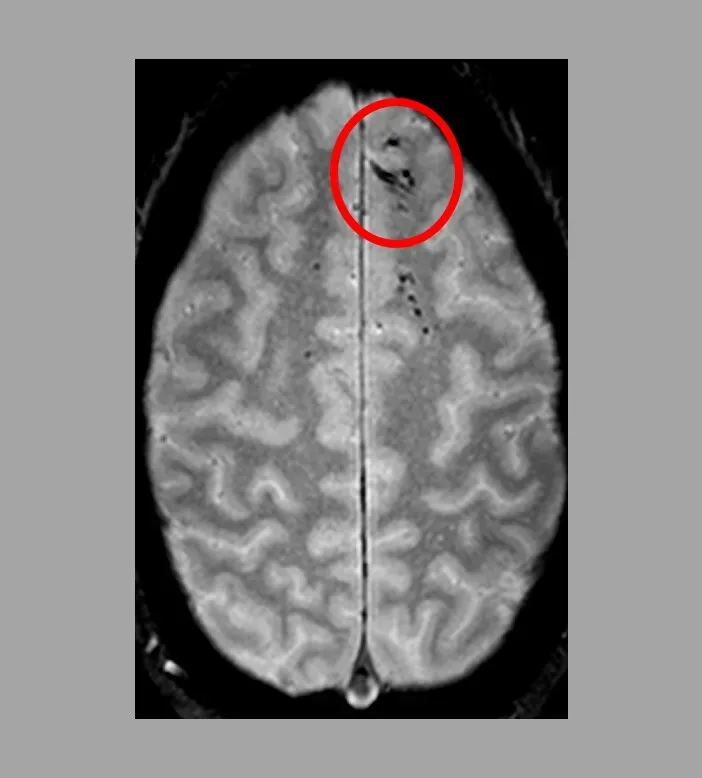

Today, powerful imaging methods like fMRI and MEG let researchers watch whole networks of brain regions coordinating as people see, hear, imagine, and dream. These tools have revealed that sensory areas are woven into loops with higher-level regions that deal with memory, expectation, and decision-making. In other words, what you sense and what you believe are constantly feeding into one another. Experiments where scientists decode what someone is looking at from brain activity alone show just how structured and interpretable these patterns can be. We are now in an era where the old philosophical hunch – reality is a mental construction – is backed by dense streams of data rather than just clever arguments.